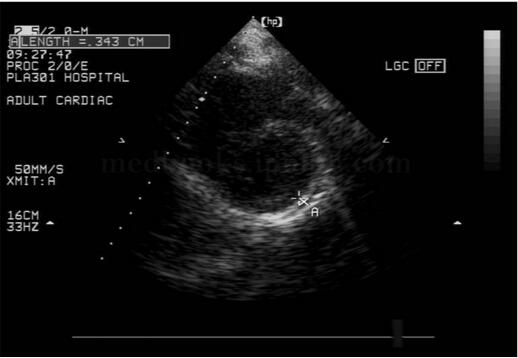

2﹒二维超声心动图 提示缩窄性心包炎的征象包括心包不同程度增厚,回声增强,尤以房室瓣环处为著,见图2‐1‐232;部分患者的心包可出现钙化,见图2‐1‐233,钙化的心包后方可出现明显的声影;四腔心切面可显示双心房增大、双心室相对较小,见图2‐1‐232;剑下四腔心切面可显示心包膜增厚、回声增强的程度,心室收缩及舒张受限;大动脉短轴及左心室长轴切面均可显示左心房增大。部分患者可出现不同程度心包积液(图2‐1‐234),心包腔内可见絮状物回声。由于心房压力增高,上下腔静脉、肝静脉扩张,且扩张的下腔静脉、肝静脉内径随呼吸变化不明显。

图2‐1‐233 缩窄性心包炎,心包钙化